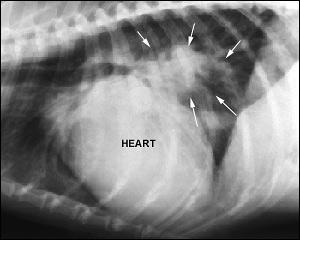

また、心臓病の種類によって病状も違うので、愛犬の病状に応じて心電図検査、X線検査、血液検査、超音波診断などを行う必要があるケースもでてくるでしょう。